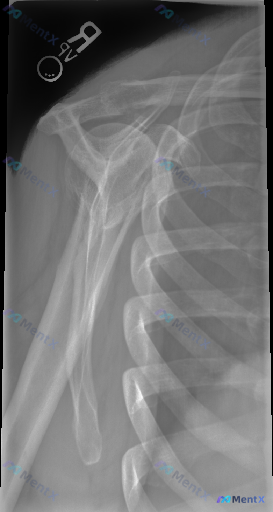

整理了一份有意思的影像资料: - 影像类型:右肩部X光正位 - 核心所见:骨骼完整性良好,肱骨近端、肩胛骨、锁骨远端骨皮质连续;盂肱关节、肩锁关节对合正常;骨小梁清晰,无溶骨/硬化/明显钙化;无骨赘形成,软组织影无明显肿胀。 - 影像总结:未见明显骨性病变。 但临床背景是「存在异常/症状」。 想先问...